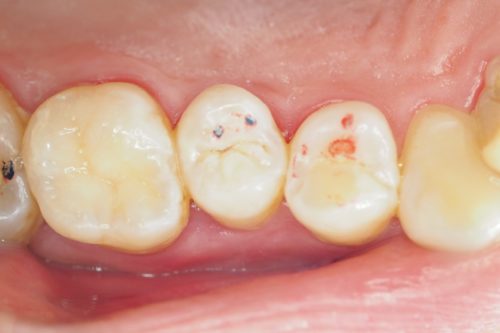

Ząb zakwalifikowano do leczenia ze względu na obecność próchnicy pod nieszczelnym wypełnieniem

Usunięto próchnicę i anatomicznie odbudowano powierzchnię żującą zęba materiałem kompozytowym